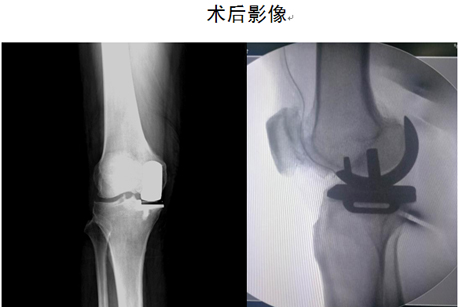

关节外科-创伤骨科主任马东印、副主任医师王兴龙通过详细查体及全面影像学检查,综合评估病情后,考虑患者为单纯右膝关节内侧间室骨性关节炎,外侧间室关节软骨尚完好,且十字韧带及内外侧副韧带也均完好。患者年龄刚六十有余,若行全膝关节表面置换为时尚早,更为可惜的是,手术需切除患者完好的外侧间室软骨及正常的十字韧带,虽能缓解疼痛,但关节功能会受很大影响,患者将不能进行深蹲、快走等灵活性活动。经过和患者充分沟通,决定为其行“右膝内侧单髁关节置换术”。经过仔细制定个体化手术及术后康复方案后,成功为患者实施了右膝关节单髁置换手术。术后第二天患者即下床活动,第五天即行走自如,彻底解决了患者疼痛及关节功能问题。

1.微创、手术切口小(10cm左右),相对于全膝关节置换手术,单髁置换手术可以说是关节置换手术中的微创手术;

2.切除骨质少,植入物小;

4.恢复快,功能好。由于创伤小,术后康复快,手术后2-3天即可下地行走,术后关节活动范围更大,运动功能更好,有些患者甚至可以进行跑步运动;